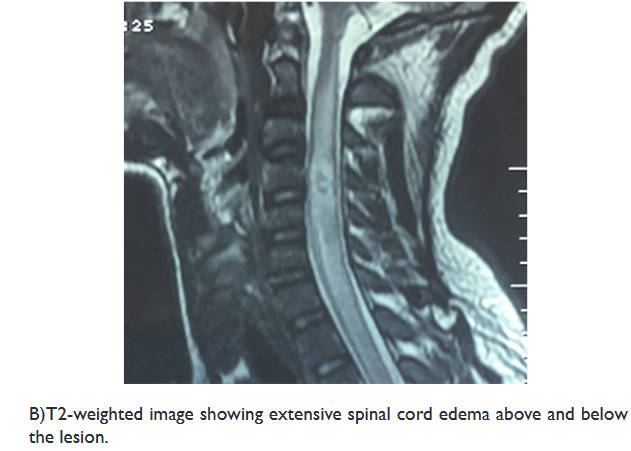

On examination, the muscle strength of the upper extremity was 2/5, and 3/5 in his lower extremity, with a positive Hoffman’s and Babinski’s signs. A spinal MRI revealed an intramedullary cystic mass, at level of C4, with ring enhancement after injection of gadolinium, associated with perilesional edema extending from the level of C2 to C7 (Figure 1).

Figure 1 Preoperative sagittal MRI of the cervical spinal cord.

Spinal MRI is the exam of choice; it provides good demonstrations of the size of the lesion, its location, and identifies any associated spinal cord abnormalities.17

Murphy et al. reported that the presentations of ISCA on MRI are similar to those of a cerebral abscess. In the early stages of infectious myelitis, MRI shows high-signal intensities on T2WI. The lesion reveals poorly defined enhancement on T1WI with contrast. One week later, the lesion becomes less diffusely hyper-intense on T2WI. The marginal enhancement is clearly defined on T1WI with contrast. Diffuse marginal cord edema was also noted.18